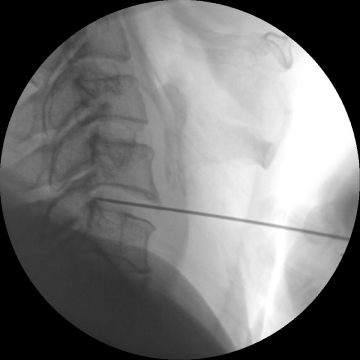

고주파수핵성형술

2017.08.07